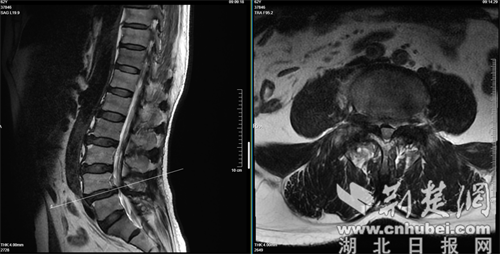

经人介绍,张先生来到襄阳市中医医院脊柱骨科就诊。经过详细的体格检查及影像学评估,张先生被确诊为腰椎滑脱症合腰椎椎管狭窄症。病变节段主要位于L4/5(腰4/5节段)。 影像显示,该节段的椎间盘退变严重,椎间隙高度塌陷,并伴有黄韧带肥厚,导致椎管内的神经根受到严重压迫。这正是导致张先生长期疼痛和无法行走的根源。

检测报告。通讯员 供图